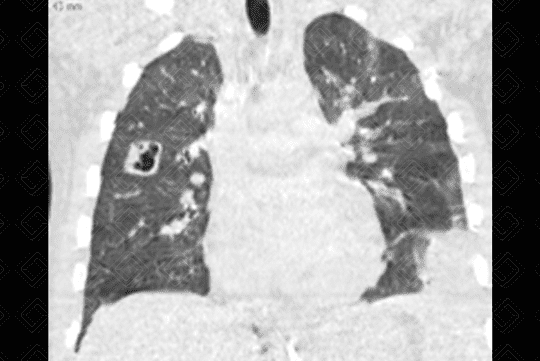

Descrição da lesão: Tomografia computadorizada do tórax (imagem axial e reformatação coronal) demonstrando opacidades nodulares bilaterais, esparsas e predominantemente periféricas, em vários estágios de escavação (setas vermelhas).

• Tomografia computadorizada do tórax: Nódulos em diferentes estágios de escavação, sendo mais numerosos na periferia dos pulmões e nos lobos inferiores. Podem ser observadas ainda consolidações geralmente subpleurais e cuneiformes.